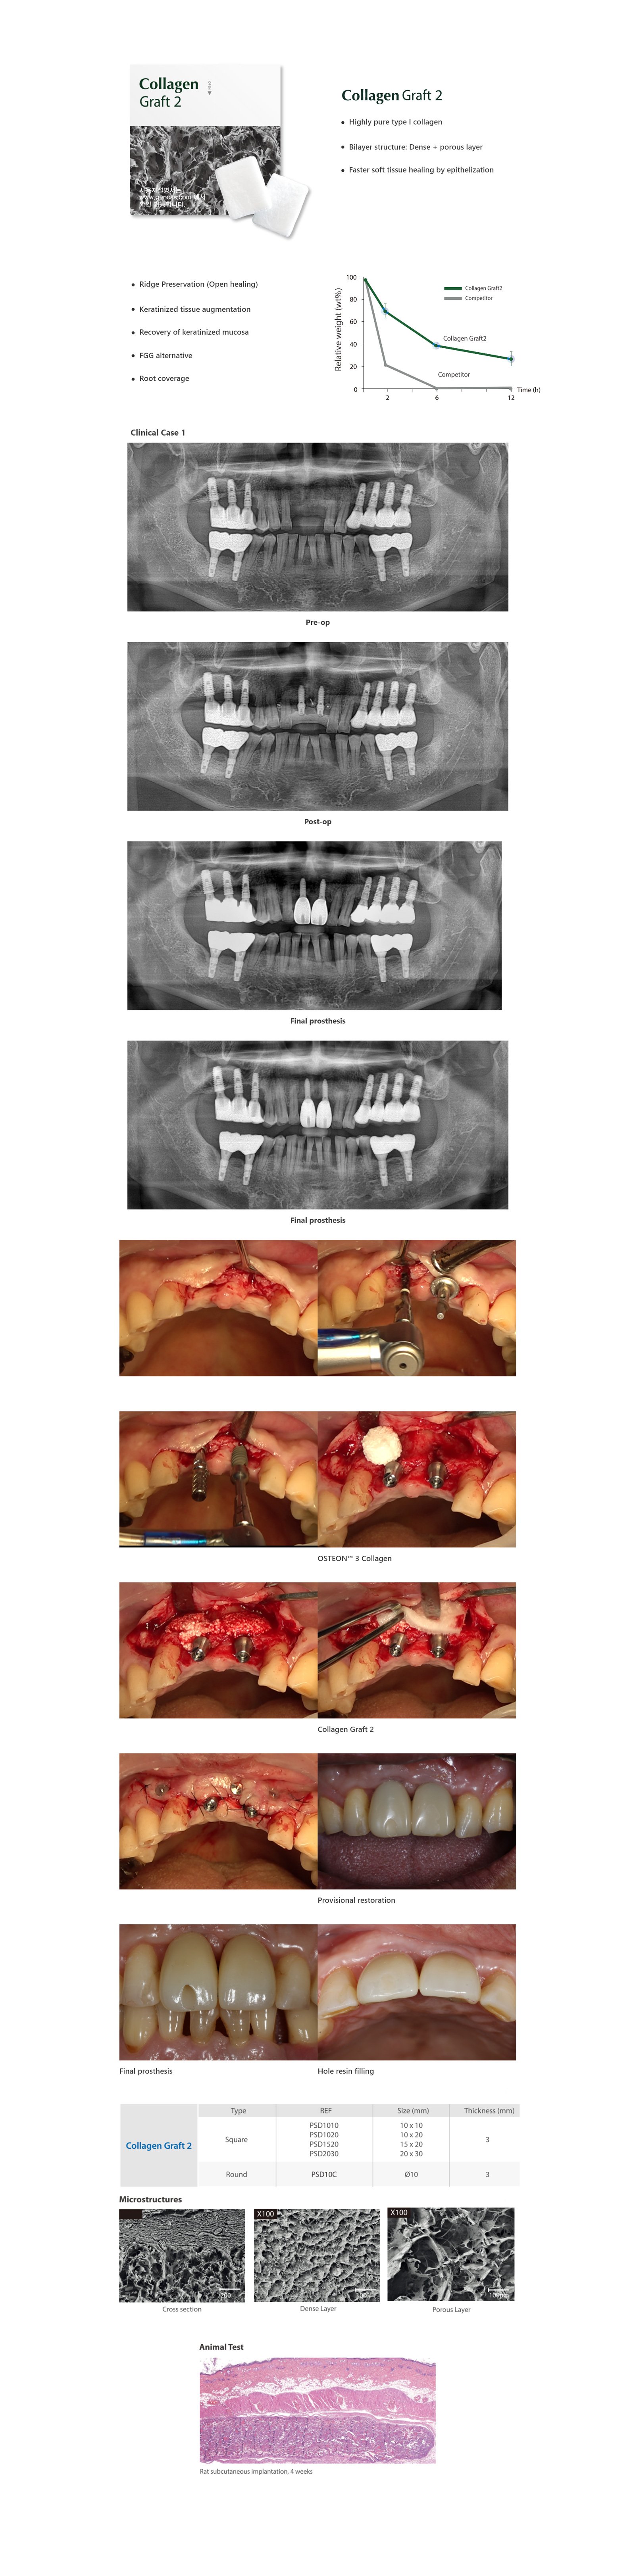

Collagen Graft 2